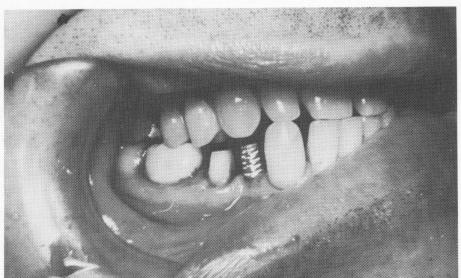

Fig. 8-54. The implant is screwed into position. The prolongator used for this case was longer than usual in order to avoid interference of the occlusal surfaces of the neigh-boring teeth with the head of the ratchet.

Fig. 8-57. An interchangeable gold coping is placed over the implant shaft.

1 Lower vent plant endosseous implant screwed into position

2 Lower vent-plant endosseous implant is seen in its proper relationship